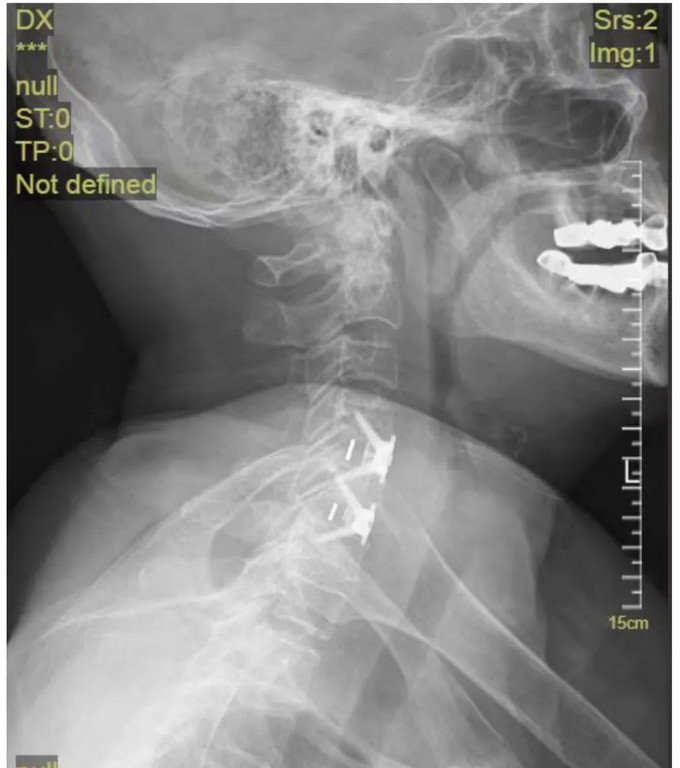

術后影像

頸椎正位DR

頸椎側(cè)位DR